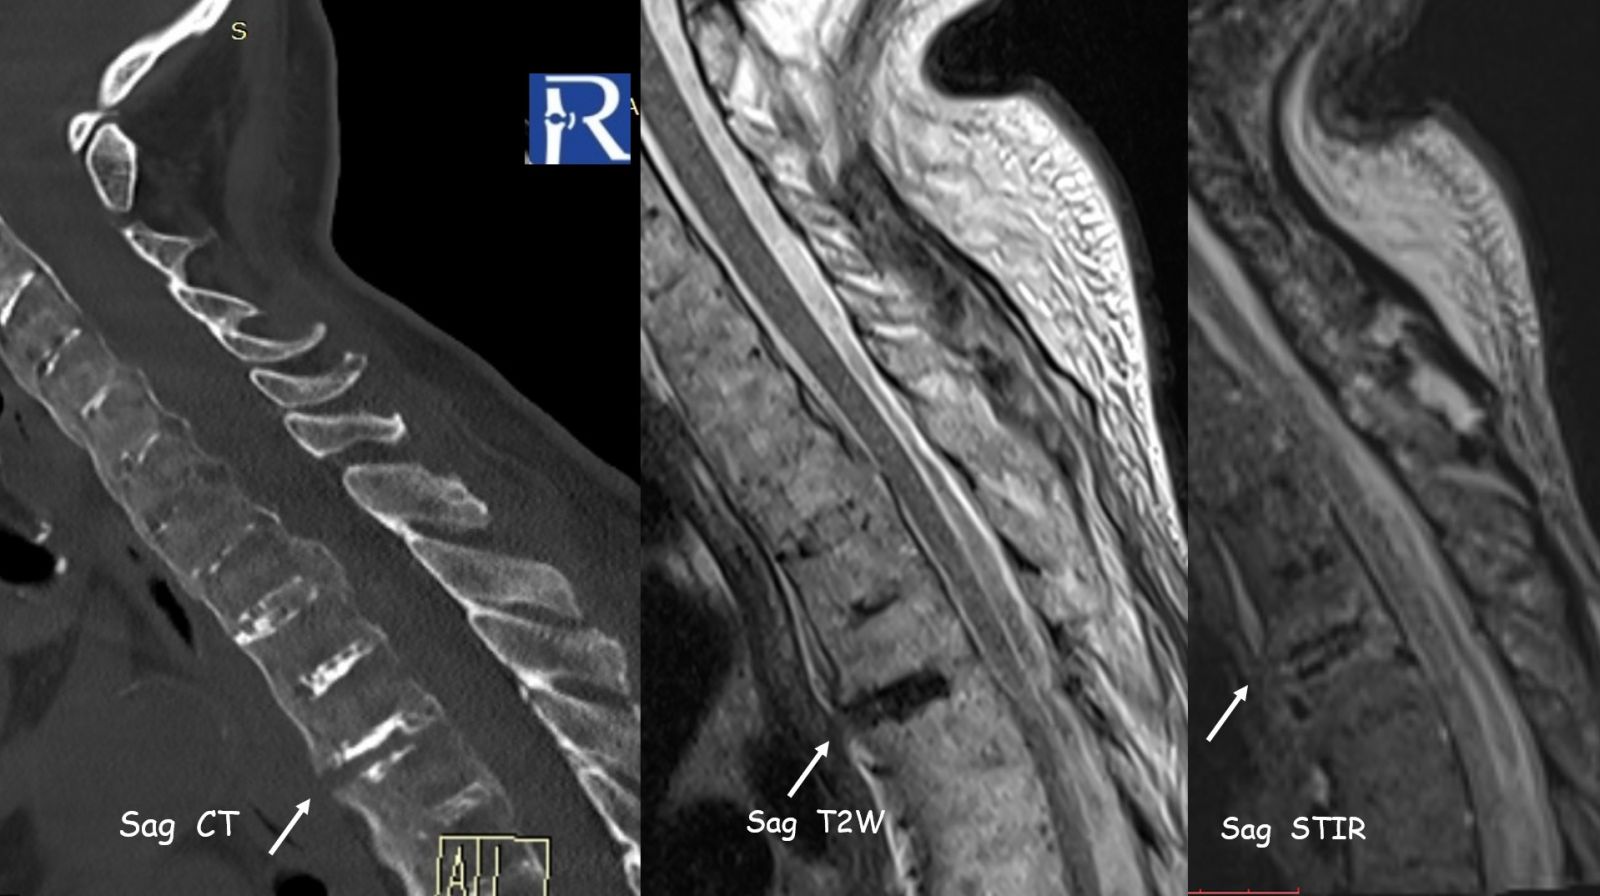

Chalk-Stick Fracture in Ankylosing Spondylitis

A 77-year-old patient with Ankylosing Spondylitis presented after a low-energy fall with acute thoracic pain.

- Extensive bridging syndesmophytes throughout the spine

- Complete spinal ankylosis (“bamboo spine” morphology)

- At the T3–T4 level, a transdiscal fracture is observed

- Fracture line extends:

- From anterior fused syndesmophyte

- Through the intervertebral disc

- Into the posterior elements (facet joints)

- Associated marrow edema and soft tissue changes on MRI

This represents a classic “chalk-stick fracture”, a transverse fracture through a rigid, ankylosed spine.

Chalk-stick fracture of the ankylosed thoracic spine